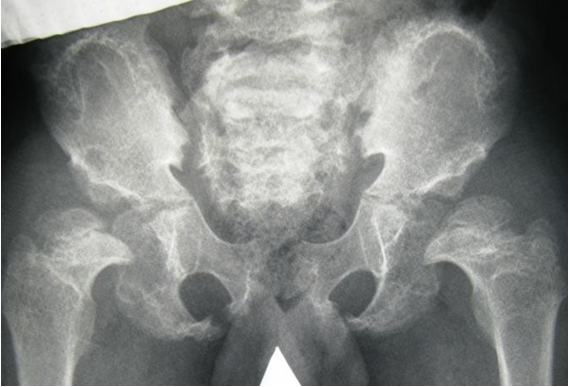

A 10-year-old boy was referred to our department because of short stature, waddling gait and skeletal maldevelopment. He was born in term after uneventful gestation, with birth length of 47 cm, and weight of 3100 g. He is the second son of the mother, but from the second marriage of non-consanguineous parents. Parents and first child are healthy without any family history of short stature, pathological gait, mental retardation and skeletal maldevelopment. His subsequent course of development has been of relative retardation in acquiring the skills of motor development. Walking has been achieved at the age of 18 months albeit with difficulty. A crouching stance was a prominent feature. Clinical examination at the age of 10 years showed: short stature (–3SD). Occipito-frontal circumference was around (–1SD). The phenotypic features were characteristic for DMC syndrome (Figure 1 [Fig. 1]). Skeletal survey and imagings were specific for this dysplasia, especially on pelvis radiographs – lacy appearance of the iliac crests were evident (Figure 2 [Fig. 2], Figure 3 [Fig. 3], Figure 4 [Fig. 4]). Hearing and vision were normal. Neurological examination was normal but intelligence was subnormal. Craniocervical 3D reconstruction CT scan showed normal atlanto-dens distance with no odontoid hypoplasia. Note the calvarial thickening of the occipital region (Figure 5 [Fig. 5]).

Figure 2: Anteroposterior pelvis radiograph showed a dysplastic pelvis. The iliac crest showed a pathognomonic, semi lunar, irregular lacy margin with a wide irregular sacro-iliac joint. Note the supero-lateral collapse of the femoral heads bilaterally causing lateral displacement of the femoral heads (associated with epi-metaphyseal irregularities). Defective ossification of the acetabuli was evident.